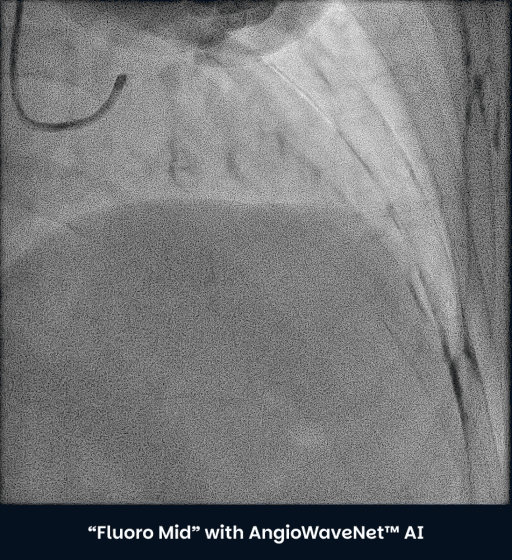

80% + Signal-to-Noise Gain

Reduced Radiation